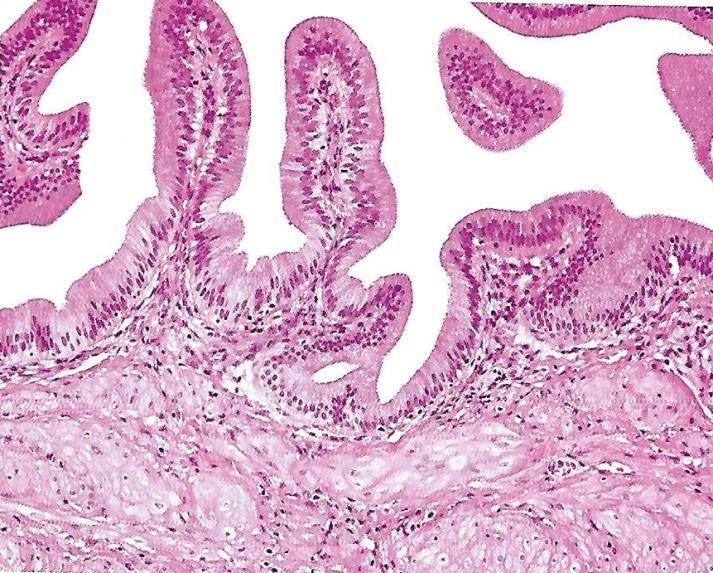

Anatomía microscópica de la vesícula biliar

La vesícula biliar vacía o con llenado parcial posee muchos pliegues de la mucosa profundos. La superficie de la mucosa está compuesta por epitelio cilíndrico simple. Las células epiteliales altas llamadas colangiocitos exhiben las siguientes características:

- Contienen numerosas microvellosidades apicales cortas y poco desarrolladas.

- Complejos de unión apicales que unen células contiguas y forman una barrera entre la luz y el compartimento intercelular

- Concentraciones de mitocondrias localizadas en el citoplasma apical y basal

- Pliegues laterales complejos.

La lámina propia de la mucosa está particularmente bien provista de capilares fenestrados y pequeñas vénulas, pero no posee vasos linfáticos. Esta capa también es muy celular y contiene una gran cantidad de linfocitos y plasmocitos. Las características de la lámina propia están especializadas en la absorción de electrolitos y agua.

La pared de la vesícula biliar carece de muscular de la mucosa y de submucosa. Por fuera de la lamina propia se encuentra una muscular externa que presenta abundantes fibras colágenas y elásticas entre los haces de células musculares lisas.

La vesícula biliar no presenta una muscular de la mucosa o una submucosa. Los haces musculares lisos están orientados de algún modo aleatorio. La contracción del músculo liso reduce el volumen vesicular, que fuerza la salida de su contenido hacia el conducto cístico.